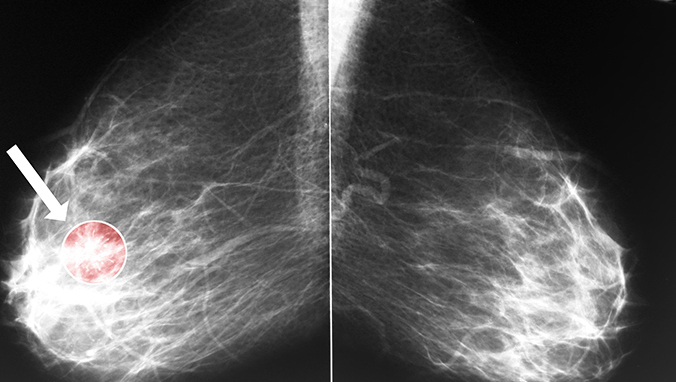

肝转移是原发性肺癌的癌细胞脱落后通过血液循环侵入肝脏并在肝脏种植生长,肝转移可以是单发或多个结节转移灶。

晚期肺癌肝转移患者表现为消瘦、肝区疼、黄疸等,血体检可发现肝大,质中或硬,边缘不规则,表面不平等肝转移特征,CEA可持续升高。清检查除谷丙及谷草转氨酶、碱性磷酸酶明显升高外,乳酸脱氢酶及r一谷氨酷基转换酶均可明显增高。早期弥漫性肺癌肝转移可无自觉症状,查体无异常发现,有时ALT或AST(谷丙或谷草转氨酶)轻中度升高,B超可有弥漫性不均质改变,应注意与其他肝脏疾病鉴别。